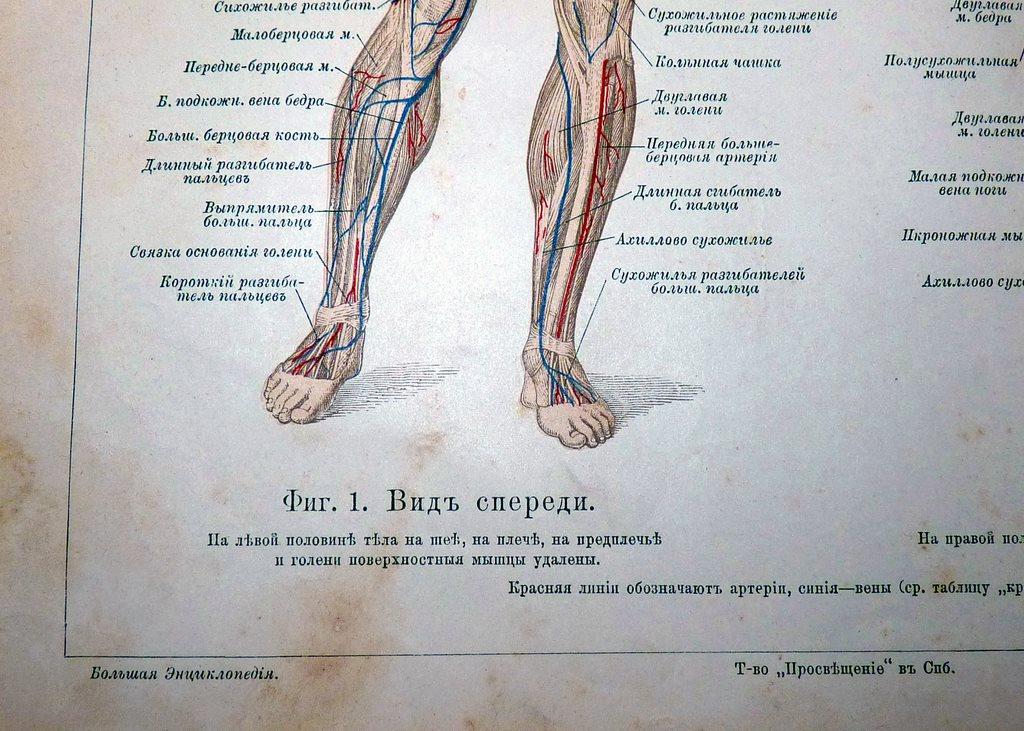

Возможные причины болей в ноге ниже колена и рекомендации